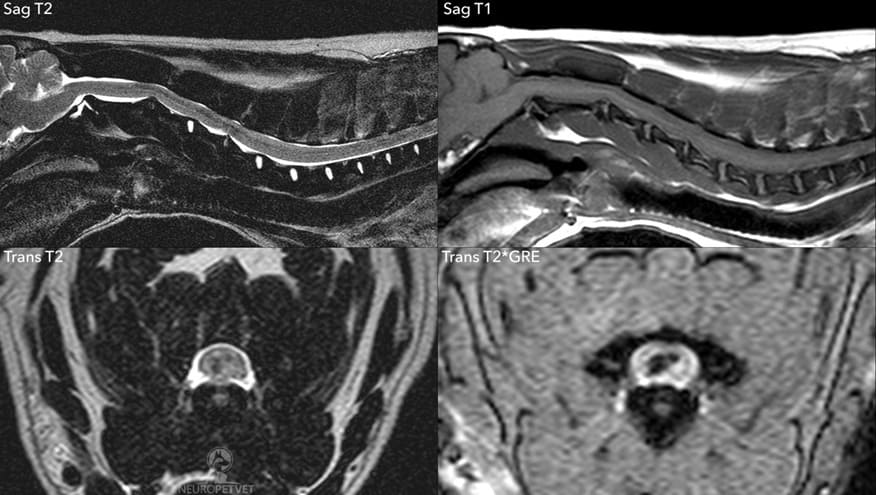

MRI από σκύλο με σύνδρομο κεντρικής μοίρας του νωτιαίου μυελού.Απεικονίζεται μία ενδομυελική αλλοίωση στην περιοχή Α4-5 με χαμηλή ένταση σήματος στις ακολουθίες T2, και στις ακολουθίες T2*GRE (HEMO), εύρημα που υποδηλώνει αιμορραγία ή παρουσία μεταλλικών/ασβεστοποιημένων υλικών.Δεν παρατηρήθηκε ενίσχυση με σκιαγραφικό (δεν φαίνεται στις εικόνες).Σημειώστε ότι ο πηκτοειδής πυρήνας του μεσοσπονδύλιου δίσκου Α4-5 είναι μικρότερος σε σχέση με τους γειτονικούς φυσιολογικούς δίσκους. Ο ασθενής διαγνώστηκε κατά προσέγγιση με οξεία μη συμπιεστική έξοδο πηκτοειδούς πυρήνα (ANNPE, “τραυματική κήλη δίσκου”) ή πιθανώς με ενδομυελική έξοδο μεσοσπονδύλιου δίσκου (μέσω ρήξης της σκληρής μήνιγγας).